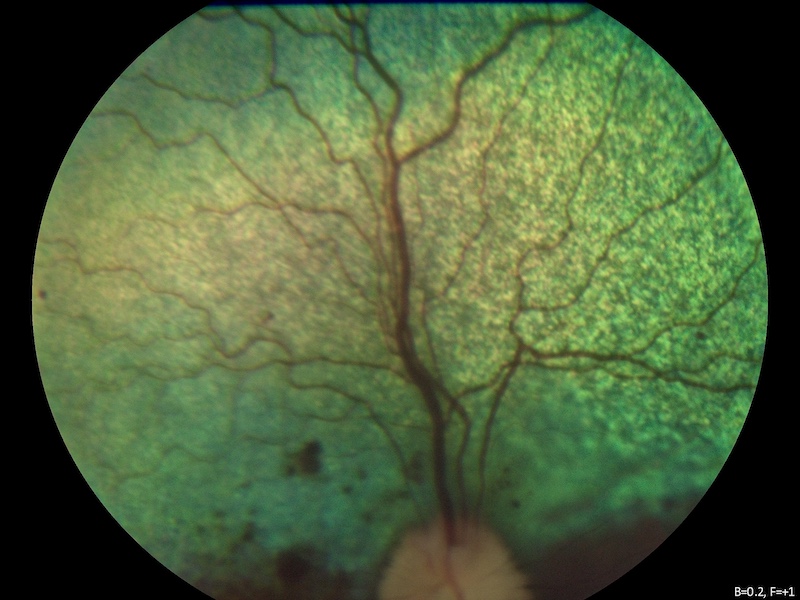

Pero hay determinados tipos de inflamaciones, especialmente de la coroides, que no se pueden ver bien con los signos clínicos externos. En estos casos hay que realizar pruebas especiales como la ecografía ocular, OCTs del segmento posterior o angiografía fluoresceínica.

Las uveítis posteriores suelen dejar en muchos casos zonas de degeneración de la retina, que también producen como secuela una pérdida de visión.